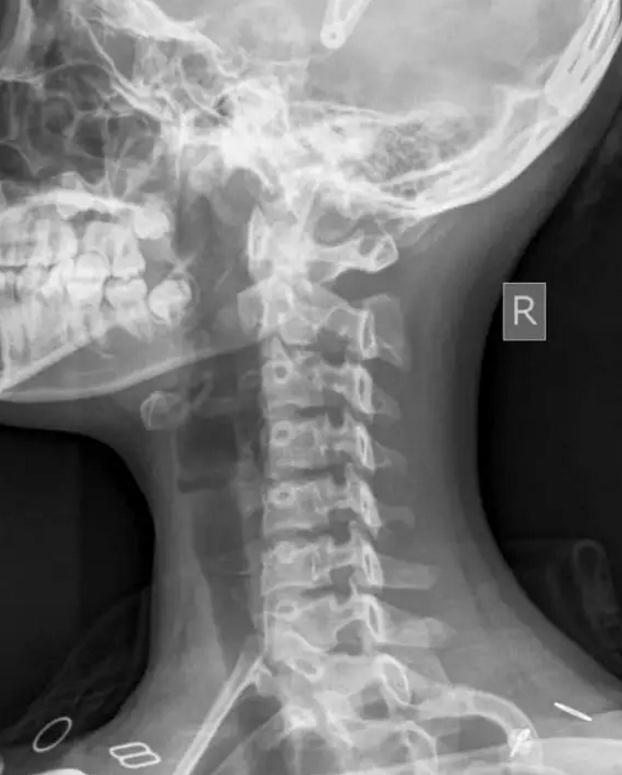

颈部下中心和部分颅骨上部中心的彩色x光片。

颈椎X光片的读片要点&常见异常改变

本文教你如何从X线片看懂颈椎病主要从神经根型颈椎病x线表现、如何看懂牙齿x片、颈椎病x线表现、颈椎病x线

在医院就诊时,一般情况下都要进行颈椎拍片检查,包括正位在X线片上可观察以下情况:1、是否有颈椎排列异.